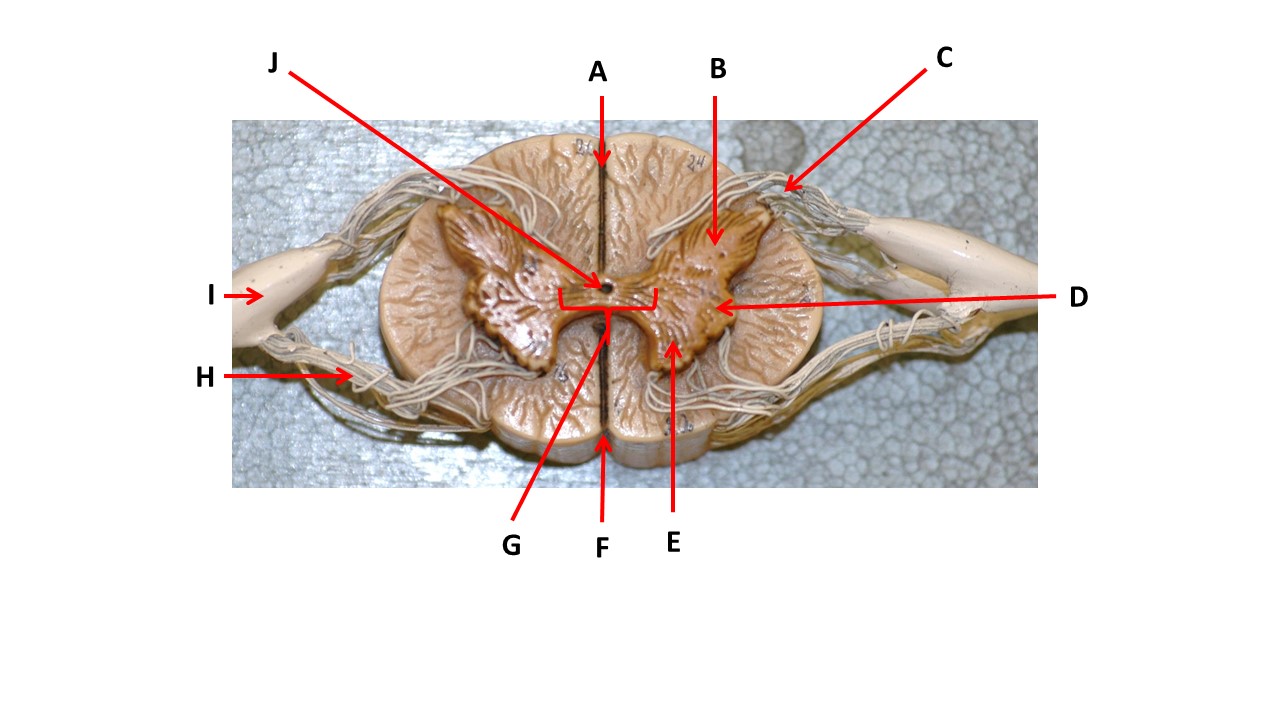

Name the region within bracket D.

Name the region of tissue surrounding the tip of arrow E.

Name the region of tissue surrounding the tip of arrow B.

Name the structure at the tip of arrow F.

Name the structure at the tip of arrow K.

Name the region of tissue surrounding the tip of arrow J.

Name the layer at the tip of arrow I.

Name the region of tissue surrounding the tip of arrow E.

Name the region of tissue surrounding the tip of arrow N.

Name the deep groove at the tip of arrow G.

Which structure(s ) would be found in the area at the tip of arrow D.

Name the region of tissue surrounding the tip of arrow E.

Name the region within bracket G.